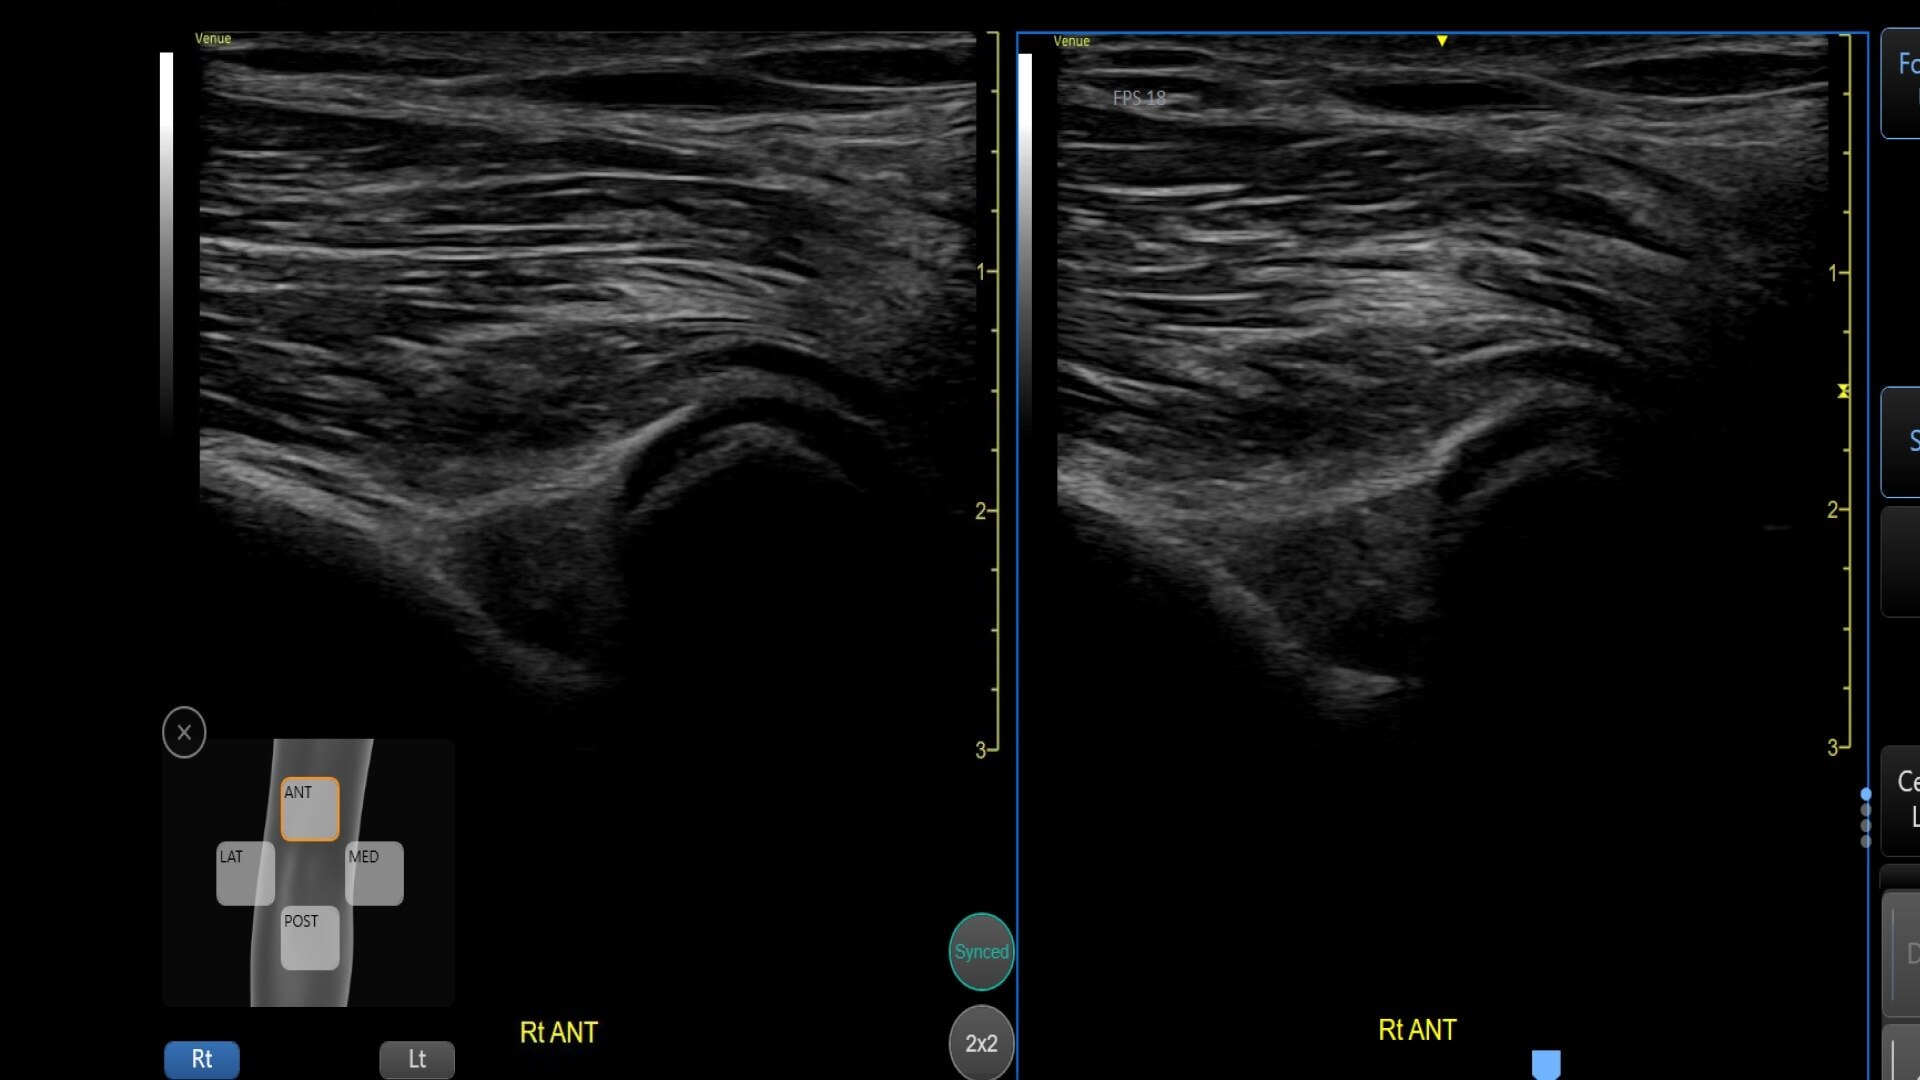

Bilateral mode: Helps you to view the opposite side of the same zone for comparison (available for Shoulder preset)